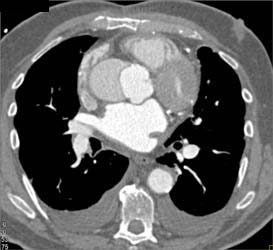

Type A Dissection